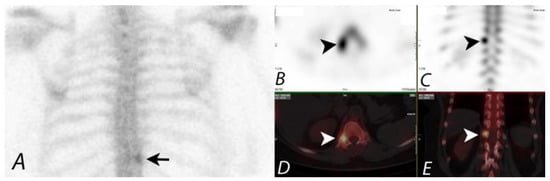

2. Oncologic Applications of Bone SPECT/CT